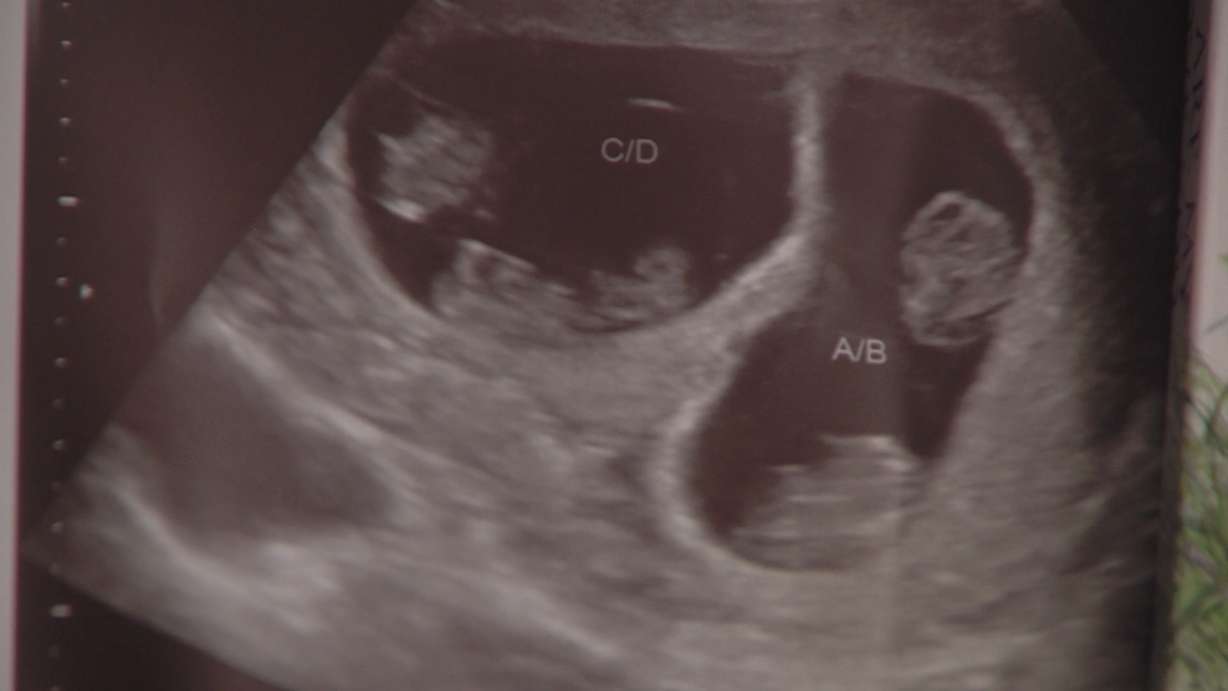

Gardner and her husband Tyson had been trying for eight years to have a child. They were stunned when they learned the two embryos that were implanted split and became two sets of identical twins.

Tyson said he initially questioned if the technician was reading the results right, but sure enough — with Ashley now 10 weeks pregnant — the four babies are taking shape and growing with each new batch of ultrasound images.